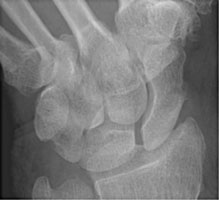

- Click on the image for a larger versionAPA radiograph of the wrist with scaphoid deviation. This view shows a fracture of the waist of the scaphoid bone.